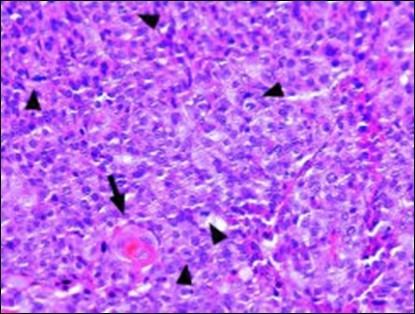

Classically, intra-epidermal and dermal nests of tumour cells exhibiting cellular atypia and enhanced mitotic activity are enunciated. Tumour aggregates articulate well demarcated, enlarged, atypical polygonal cells with indistinct cellular and nuclear outline, nuclear hyperchromasia , irregular nuclei, vesicular or prominent nucleoli and minimal eosinophilic cytoplasm. Polygonal tumour cells can depict central keratinisation 6, 7.

Granular arrangement of malignant cells and intercellular bridges are conspicuous with the demonstration of nuclear atypia, pleomorphism, prominent mitosis and tumour necrosis. A peripheral palisade is discernible within the cellular aggregates. Mitotic figures are common and can be quantified as up to 12 mitosis/ high power field. Tumour differentiation can prominently be of the ductal category with the demonstration of intra-cytoplasmic lumina. Comedo type tumour necrosis is evident along with foci of squamous differentiation The neoplasm is reactive to periodic acid Schiff ‘s (PAS) stain. (Figure 1, Figure 2, Figure 3, Figure 4, Figure 5, Figure 6, Figure 7, Figure 8, Figure 9, Figure 10, Figure 11, Figure 12, Figure 13.

Figure 4.Cellular atypia, mitosis and focal necrosis in eccrine porocarcinoma(16).

Figure 8.Disseminated atypical epithelial cells with cellular and nuclear pleomorphism, hyperchromasia, indistinct cytoplasm, vesicular nucleoli and central keratinization in eccrine porocarcinoma(20).